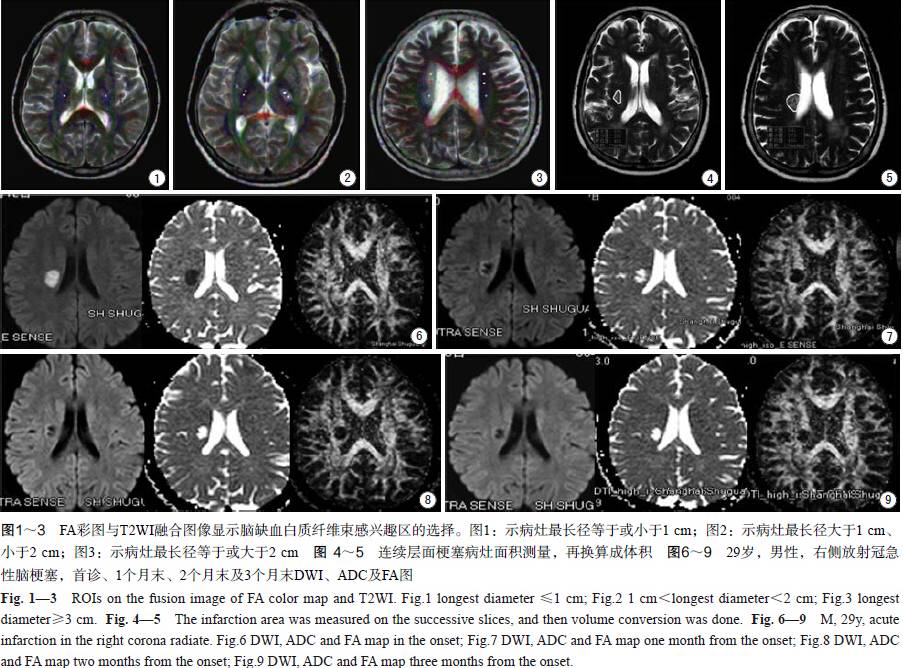

将所得扩散张量原始图像传入Philips View Forum (ExtendedMR Work Space 2.6.3.1)后处理工作站,由1名已从事磁共振神经系统影像诊断12年的医师使用Fiber Tracking软件进行统一标准的图像后处理。计算部分各向异性指数(fractionalanisotropy,FA)和表观扩散系数(apparent diffusion coefficient,ADC)。感兴趣区选取标准:根据DWI及T2WI图像上每个层面病灶的大小取感兴趣区:病灶最长径等于或小于1 cm的取1个感兴趣区,最长径在1~2 cm之间的取2个感兴趣区,最长径等于或大于2 cm的取3个感兴趣区(图1~3);同时在对侧镜像脑白质取对照区。感兴趣区及对照区的大小均为一个像素值。根据每个层面病灶感兴趣区和对照区获得FA值和ADC值分别计算FA比值(rFA)和ADC比值(rADC),并取平均值。计算梗塞体积:于PACS(东软,中国)上先参考DWI图像,再于T2WI序列梗塞病灶每个层面上沿病灶边缘手工划取得到面积(图4~5),乘以6 mm [层厚(5 mm)加层间距(1 mm)],得到每层的体积,最后病灶各层面体积值相加得到总体积。

首诊40例急性缺血性脑白质损伤并有运动功能障碍患者[左侧18例,右侧22例;首诊MI范围1~96.5分,x±s:(70.3±28.6)分]中,梗塞累及多处脑白质8例,放射冠17例,内囊5例,胼胝体1例,上纵束2例,脑干皮质脊髓束4例,大脑脚、外囊和丘脑辐射各1例。首诊急性期梗塞灶DWI为高信号,FA及ADC为低信号;1个月末梗塞灶DWI为低或稍高、低混杂信号,FA为低信号,ADC为高或高、稍低混杂信号;2个月末和3个月末梗塞灶DWI及FA为低信号,ADC为高信号,病灶范围随时间推移而逐渐减小(图6~9)。40例患者于各个时间点rFA(FA值病灶/镜像侧)、rADC(ADC值病灶/镜像侧)和梗塞体积的统计结果见表1。